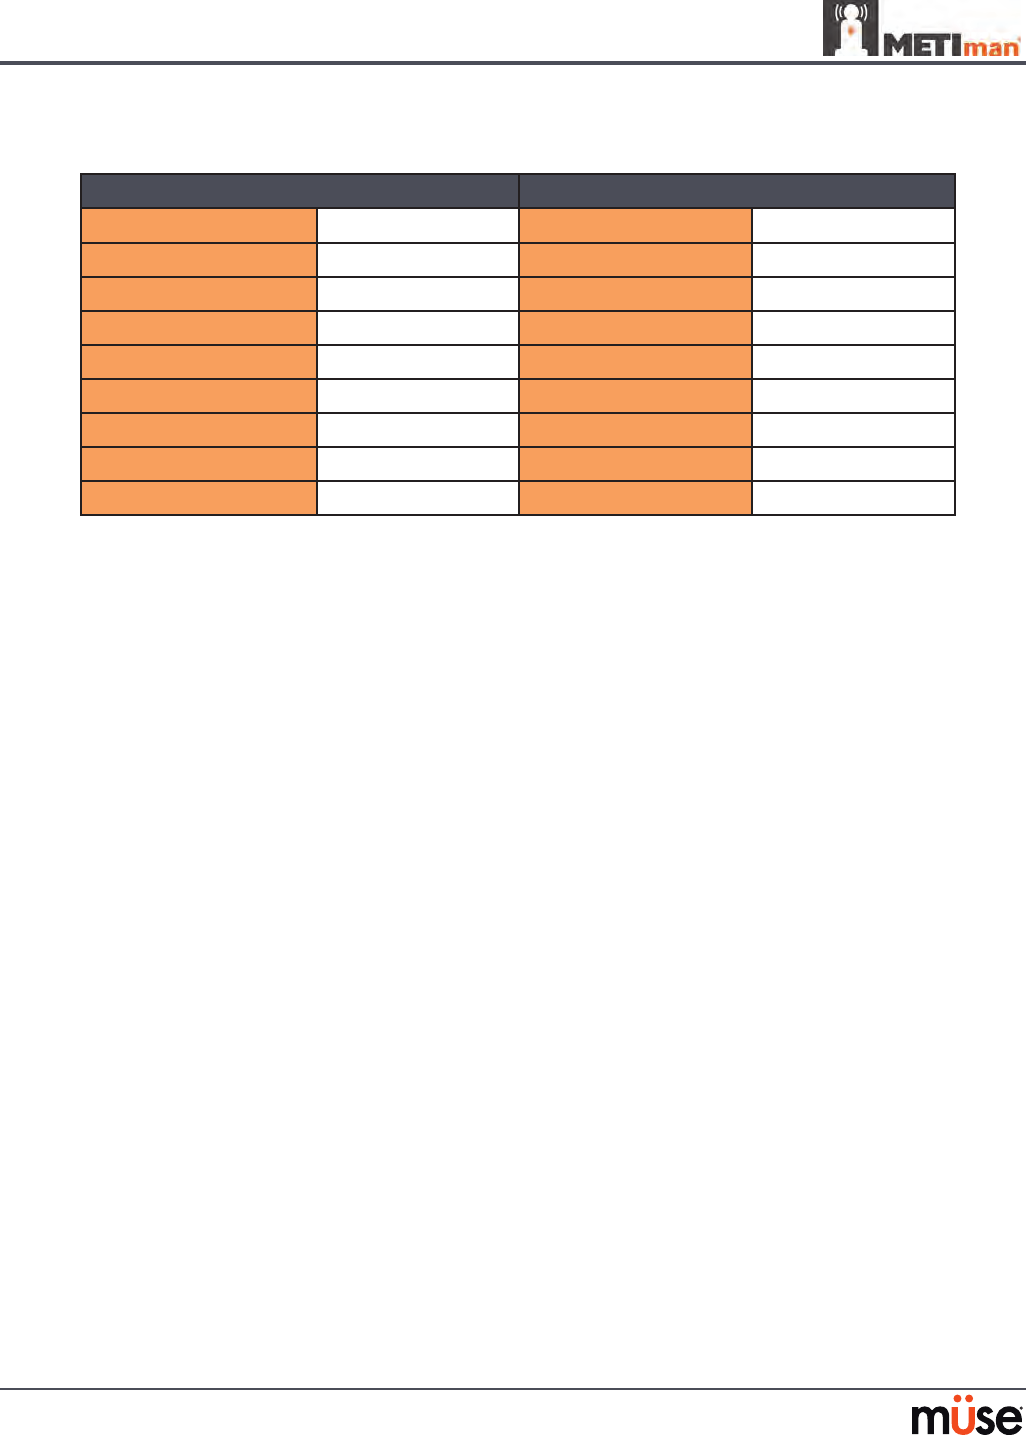

Airway Features

Anatomy, Physiology

and Clinical Signs Clinical Interventions, Patient

Monitoring and Scenarios. Software Control Manual

Control

Realistic Upper

Airway (Oropharynx,

Nasopharynx and Larynx)

(Prehospital only)

Allows direct laryngoscopy, oral and

nasal intubation and use of specialty

airway devices. Simulator detects

and responds appropriately to right

mainstem intubation. Endobronchial

intubation results in unilateral chest

excursion and breath sounds.

None required. None required.

Trachea, Left and Right

Mainstem Bronchi

(Prehospital only)

Tracheal intubation results in bilateral

chest excursion and breath sounds. None required. None required.

Airway Management and

Ventilation

Alveolar and arterial gas concentrations

appropriately reect the ecacy of

ventilation and oxygen administration.

Oxygen

administration input

by the instructor.

VIEW: Respiratory

None required.

Gastric Distention

(Prehospital only)

Esophageal intubation results in gastric

distension and the absence of breath

sounds, chest excursion and CO2 output.

None required. None required.

Breakaway Teeth

(Prehospital only)

Upper front teeth can be dislodged if

laryngoscopy is performed incorrectly. None required. See Breakaway

Teeth

Tongue Edema

(On/O)

Hinders, but does not prevent,

intubation. VIEW: Respiratory None required.

Posterior Pharynx

Swelling

(Prehospital only)

Obstructs view of larynx to prevent

intubation, but allows mask ventilation

“can’t intubate, can ventilate” scenario.

VIEW: Respiratory None required.

Laryngospasm

(Prehospital only)

Closes vocal cords and prevents

intubation and ventilation. When used

with posterior pharynx swelling, creates

a “can’t intubate, can’t ventilate” scenario.

VIEW: Respiratory None required.

Cricothyroid Membrane Allows needle cricothyrotomy,

transtracheal jet ventilation, retrograde

wire techniques and cricothyrotomy.

None required. See

Cricothyrotomy,

132